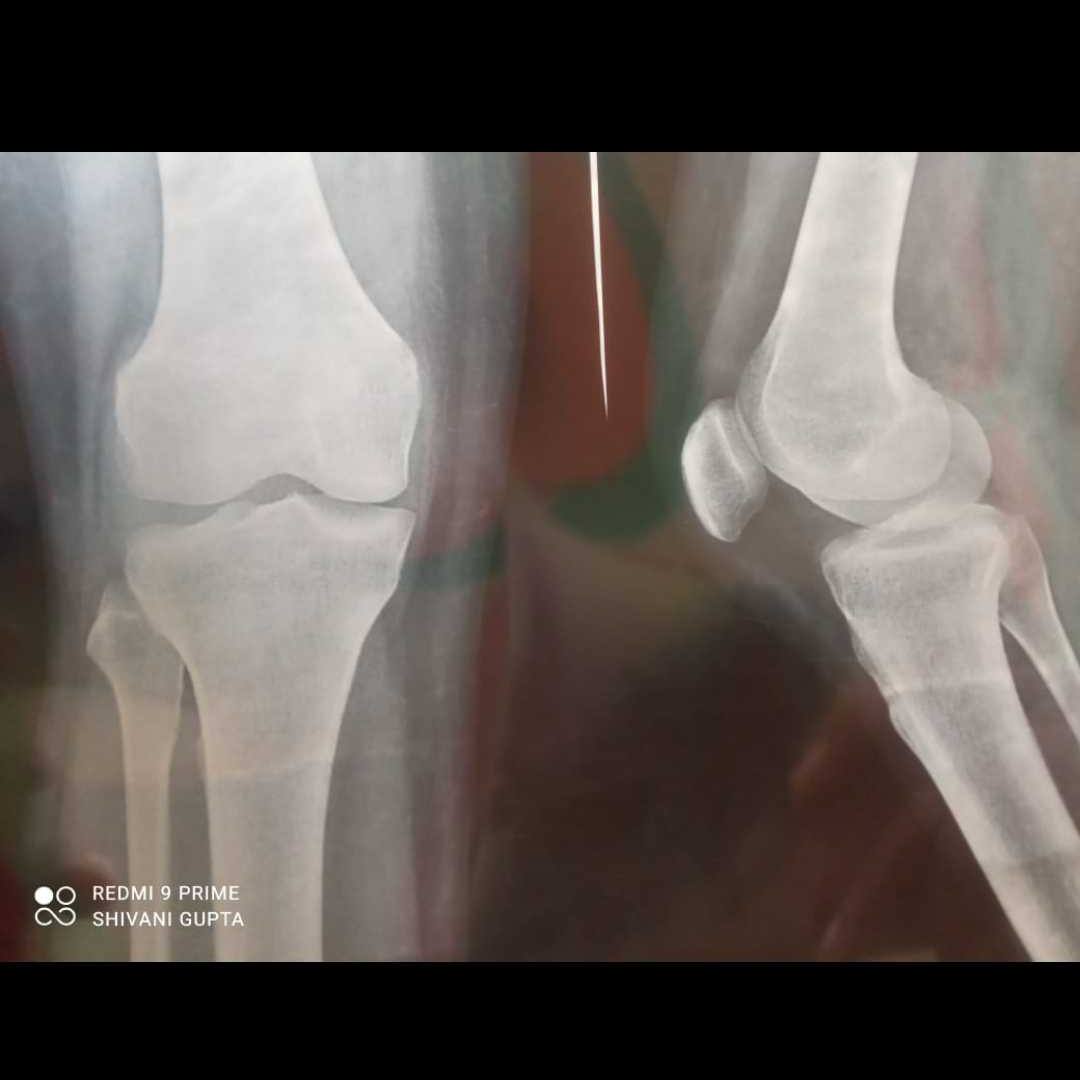

sir mere ghutne se lekar pure pairo me thoda sa bhi chalne per tej dard hone lgta hai please kuch btaye sir xray dekhkar.